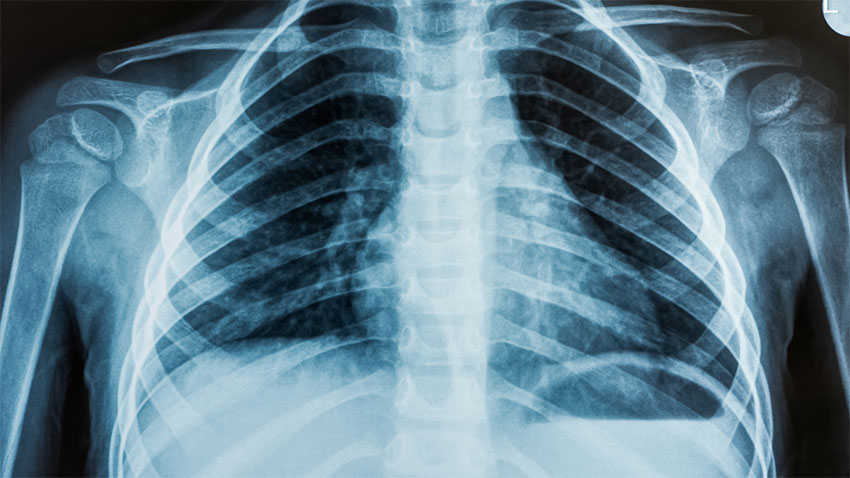

Explore Our Main Services

When you visit one of our state-of-the-art clinics we will make your examination as comfortable as possible with easy parking, spacious, private change rooms and comfortable waiting areas.